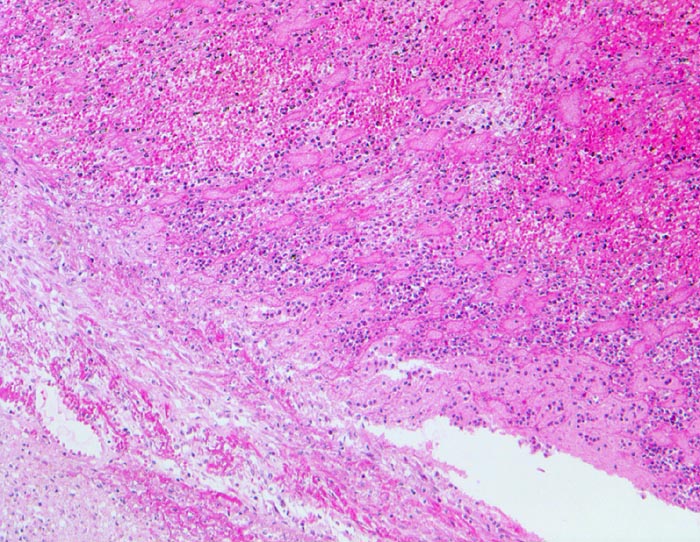

PathoPic ID 4544 - Parietalthrombose über Myokardinfarkt

Parietalthrombose über Myokardinfarkt

vaskulär / Durchblutungsstörung

Herz links

Kardiovaskuläres System

Über dem Infarkt, dem

Endokard aufgelagerter geschichteter Korallenstockthrombus bestehend aus

Fibrin,

Granulozyten und

Erythrozyten.

Diagnose eines Myokardinfarktes vor 4 Tagen.

Histologie

50